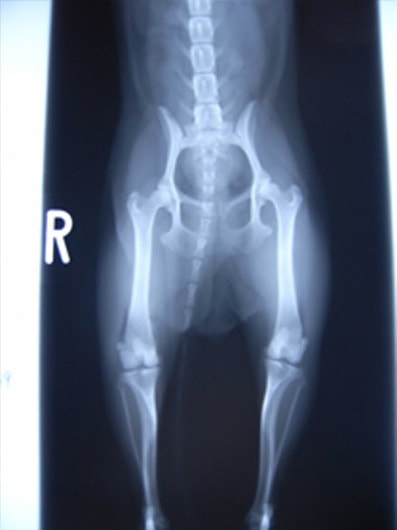

■ 症例20 ポメラニアン 8ヶ月 1.8kg

左右膝蓋骨脱臼 グレードⅢ

2ヶ月前から間欠的跛行が認められ、両膝の膝蓋骨脱臼整復術を行った。

手技は縫工筋及び内側広筋の解放、脛骨粗面の外側転位、滑車ブロック形造溝術、内外側関節包の縫縮を選択し実施した。

右側の膝蓋骨脱臼は上記手技で整復されたものの、左側はそれのみでは膝蓋骨が浮く様子が認められた。その為、PDS縫合糸にて膝蓋靱帯を1糸のみ縫合し、靱帯の縫縮を行った。

膝蓋骨脱臼は膝関節における膝蓋骨の内外側の脱臼と定義されるが、時として単純な内外の脱臼ではなく、膝蓋骨が大きく前方に浮き上がるように脱臼する場合がある。特にトイプードルやポメラニアンといった犬種に多く認められる。

内側脱臼に加えて前方への浮き上がりを矯正する為に、従来より脛骨粗面転移により膝蓋靭帯を外方と下方に引っ張り、固定する方法を選択する。膝蓋骨の前方への浮き上がりが軽度の場合は、従来法ではなく関節包の縫縮で対応していた。しかし、一部の症例で膝蓋骨の動きが悪くなり伸展機構が円滑に機能せずロボット様歩行になるケースがあった。

その為、膝蓋靭帯自体を縫縮する方法を採用した。この方法により、膝関節の伸展機構を妨げず膝蓋骨の軽度の浮きを矯正することが可能となった。

本症例の経過は良好である